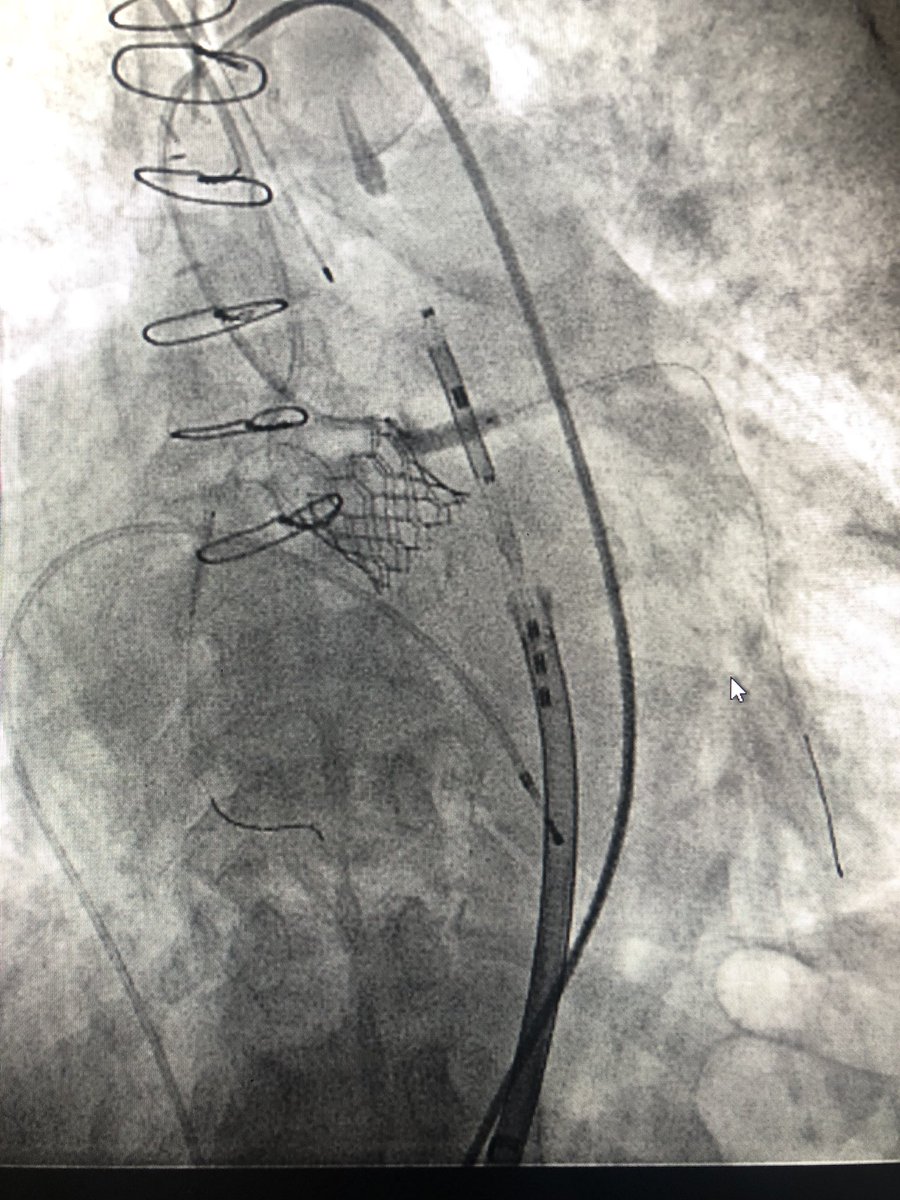

#TAVR #doubleprotection 56 yo f w/ SAVR 23 mm Freestyle. No CAD, ESRD. Severe prosthetic AS for ViV TAVR. Low RCA height at 6.8 mm and LCA at 8.1 mm. 23mm S3 deployed after protection of both coronaries. Post angio compromise of both cors. LM/RCA stents deployed w/ good result.

KaliyadanMD's tweet image. #TAVR #doubleprotection 56 yo f w/ SAVR 23 mm Freestyle. No CAD, ESRD. Severe prosthetic AS for ViV TAVR. Low RCA height at 6.8 mm and LCA at 8.1 mm. 23mm S3 deployed after protection of both coronaries. Post angio compromise of both cors. LM/RCA stents deployed w/ good result.